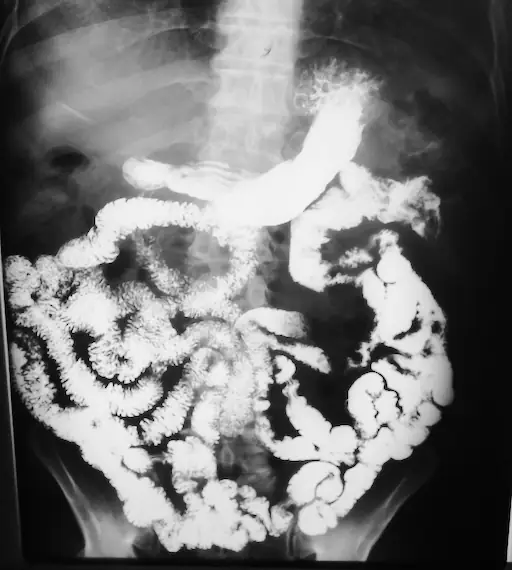

9. Intestino Delgado

Segmento intestinal responsable de la absorción de nutrientes y micronutrientes. Es un organos con dificultades para su evaluación por estudios de imagen.

Tomografía/Resonancia (8/10): Protocolos de enteroclisis o entero-TC para la detección de enfermedad inflamatoria intestinal.

Radiología con Contraste (6/10): Tránsito intestinal para evaluar la cinética del medio de contraste.

Ecografía (3/10): Limitada por el meteorismo abdominal.

Nota: La cápsula endoscópica es la herramienta de mayor sensibilidad para la visualización de la mucosa del intestino delgado.